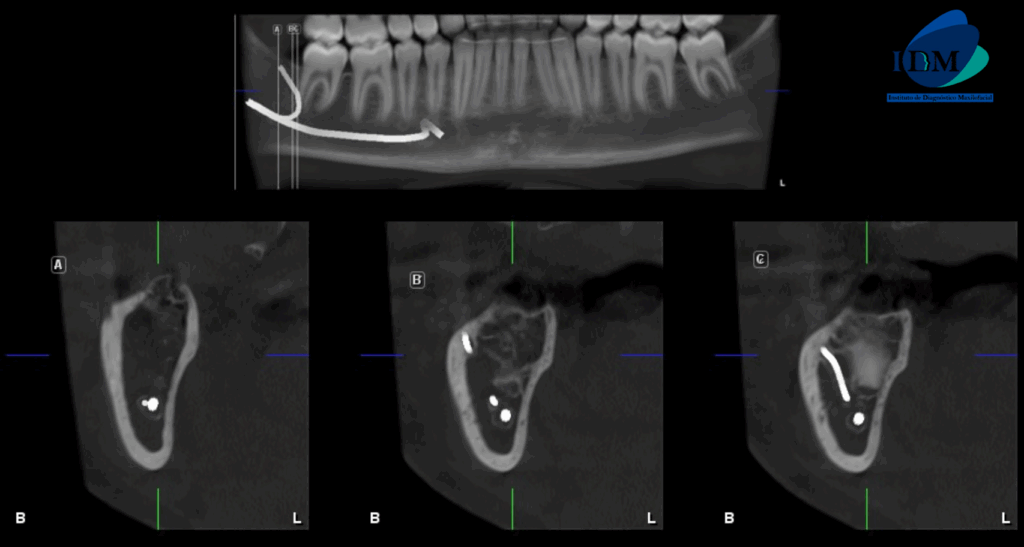

A la evaluación de la tomografía volumétrica (CBCT) en los cortes axiales (Figura 2) y transaxiales (Figura 3), se aprecia se aprecia bifurcación del conducto dentario inferior del lado derecho.

CORTES TRANSAXIALES

- Bifurcación de conducto dentario inferior

La bifurcación del conducto dentario inferior (BCDI) es una variante anatómica del canal En la mandíbula, es posible observar anatómicamente una bifurcación del conducto mandibular, dividiéndose en dos ramas separadas que discurren por canales independientes, cada uno alojando su propio paquete neurovascular. Esta variación anatómica puede presentarse unilateral o bilateralmente a lo largo de la rama mandibular.

Reconocer la ubicación y la configuración del conducto dentario inferior es fundamental en cualquier procedimiento quirúrgico bucal que involucre la mandíbula, como la extracción de terceros molares, la colocación de implantes dentales o la realización de una osteotomía sagital de rama. Una identificación precisa de esta estructura permite minimizar riesgos y evitar posibles complicaciones neurovasculares durante la intervención.